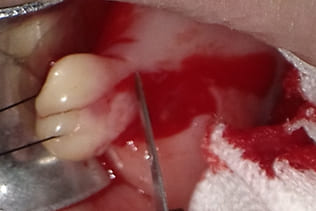

局所浸潤麻酔を行い、腫瘍に糸をかけ、十分にカウンタートラクションをかけた状態で、メスで腫瘍に沿って木の葉状に切開し、牽引しながらメスで周囲の結合組織と腫瘍の境界を鋭利に剥離する。切る感じではなくて削ぐ感じでメスを用いることが重要である。